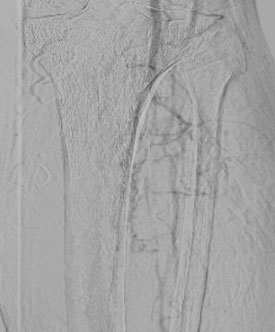

- Следующим этапом выполнена механическая реканализация и баллонная ангиопластика артерий голени.

Ангиографическая картина голени перед баллонной ангиопластикой |

| Ангиографическая картина после баллонной ангио пластики | |

Контрольная ангиография показала полный успех: герметичные швы, состоятельные анастомозы и, главное, – восстановленный кровоток по всем сосудам левой нижней конечности до пальцев.